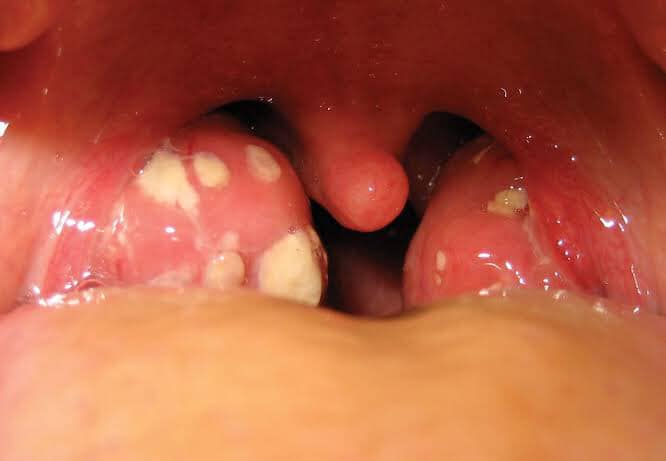

التهاب اللوزتين والحمى الروماتيزمية

اللوزتين جزء من الحلق والاثنين يلتهبان عند حدوث عدوى من مختلف الميكروبات من فيروسات وبكتيريا ومن أشهرهم بكتيريا الميكروب السبحي التي تتسبب في الحمى الروماتيزمية، والتأخير في علاج عدوى الميكروب السبحي وسوء استخدام المضادات الحيوية يؤدي إلى بقاء العدوى مدة طويلة بالمصاب وهذا هو ما يتسبب في نشوء الحمى في ٣% من الحالات.

ولا يصيب الميكروب السبحي اللوز فقط ولكن يصيب الحلق والجلد والمسالك البولية، والعدوى باللوز ليست الوحيدة التي تسبب الحمى ولكنها الأشهر نظرا لتكرارها وطول مدتها ان لم تعالج سريعا.